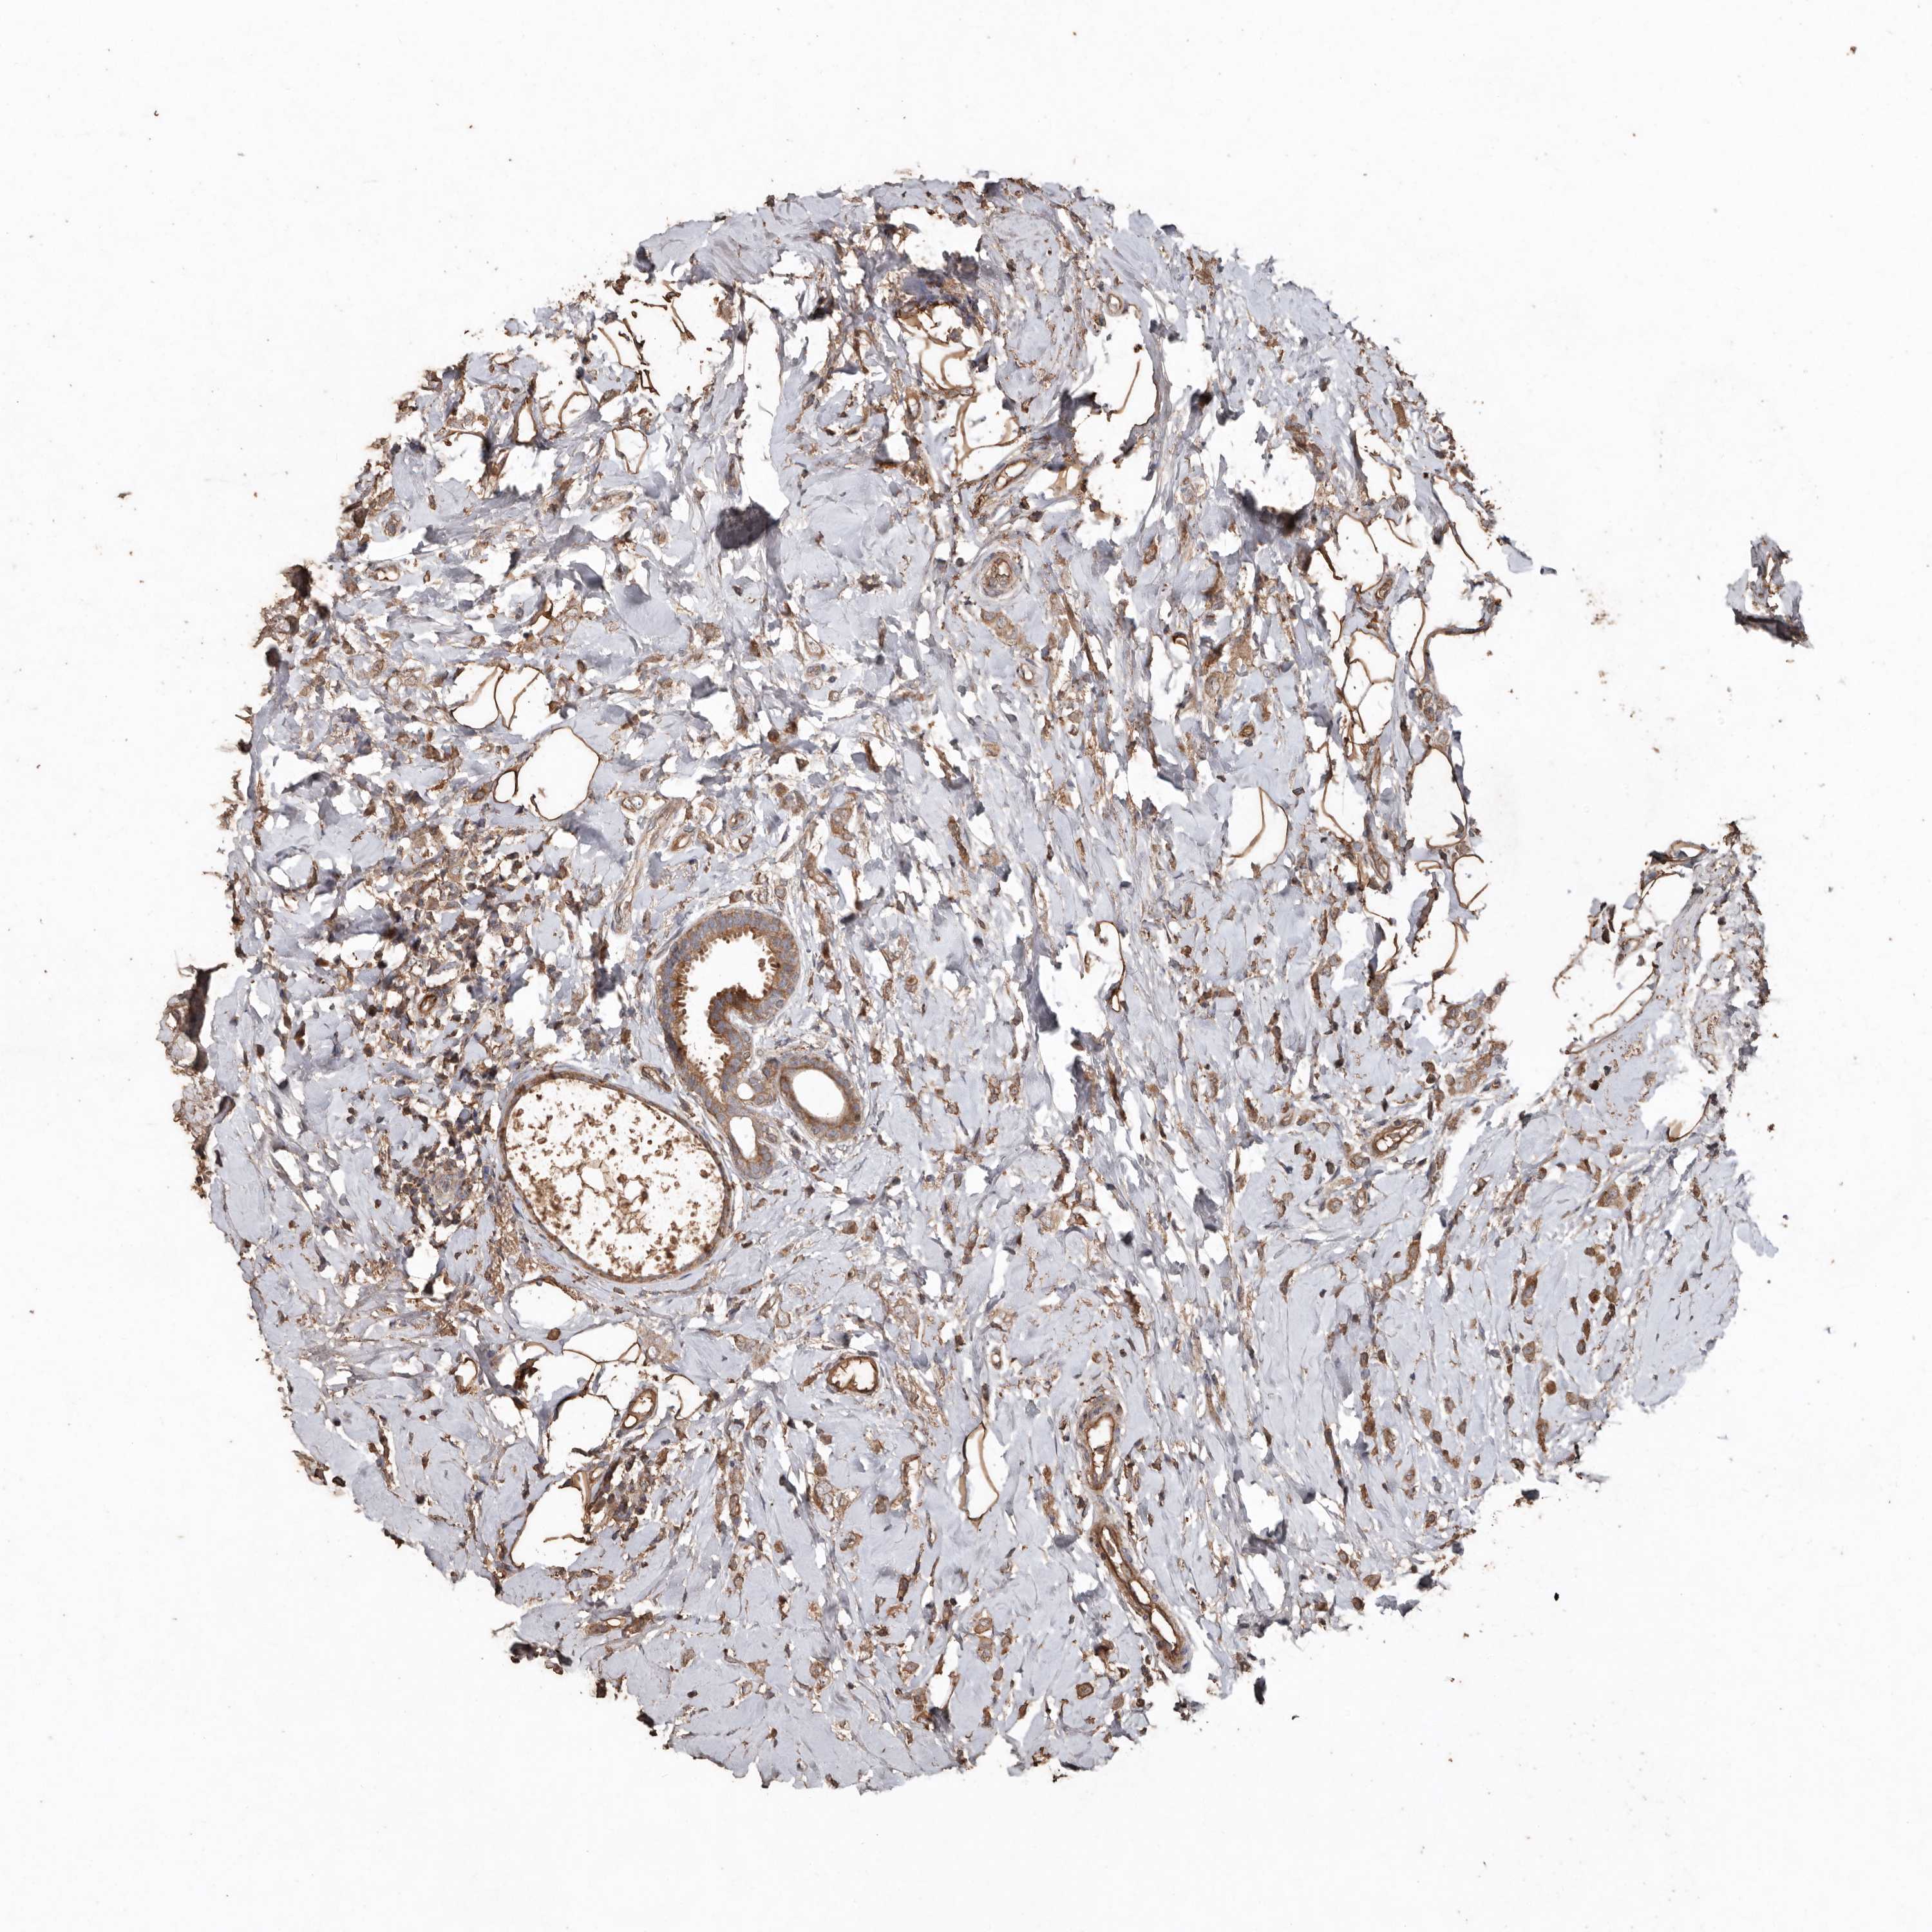

CANCER BREAST CANCER Show tissue menu

BRCA TCGA BRCA VALIDATION PROTEIN EXPRESSION